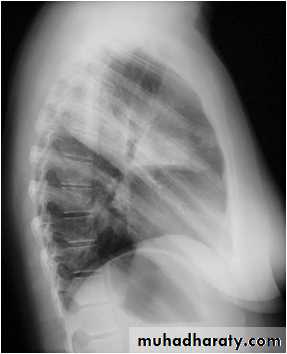

Right middle lobe collapse has distinctive features, and is usually relatively easily identified.

Radiographic features

Chest radiograph

Frontal chest XR showing opasity cause obscuration of the RT cardiac border

Lateral chest XR film the opacity is tongue like shape

versus (triangular in shape) in RT middle lobe consolidation seen in lateral chest XR film

RT middle lobe consolidation

RML consolidation